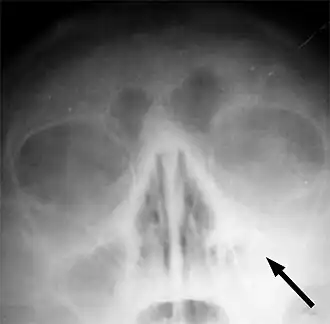

![]() Radiografía que muestra congestión de orificio nasal maxilar izquierdo indicado por una flecha. | ||